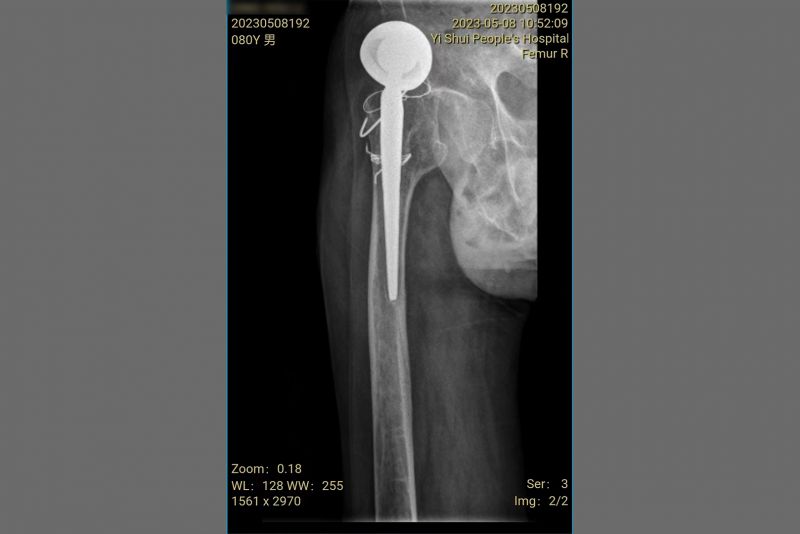

术前影像资料。

患者的患肢较对侧缩短4厘米。

孙冰主任带领南院骨科医疗团队对患者的病情进行分析讨论,综合病史、临床表现及相关影像学检查,一致认为:患者右髋关节疼痛及活动受限主要由右侧人工股骨头假体上移、假体功能障碍所致。鉴于患者的病情复杂,医生先通过3D打印技术,打印模型,预演手术,并对术中潜在的风险进行了全面的评估。最终,科室制定了较完善的全髋关节假体翻修术的手术预案以及围术期详细的治疗及护理方案。